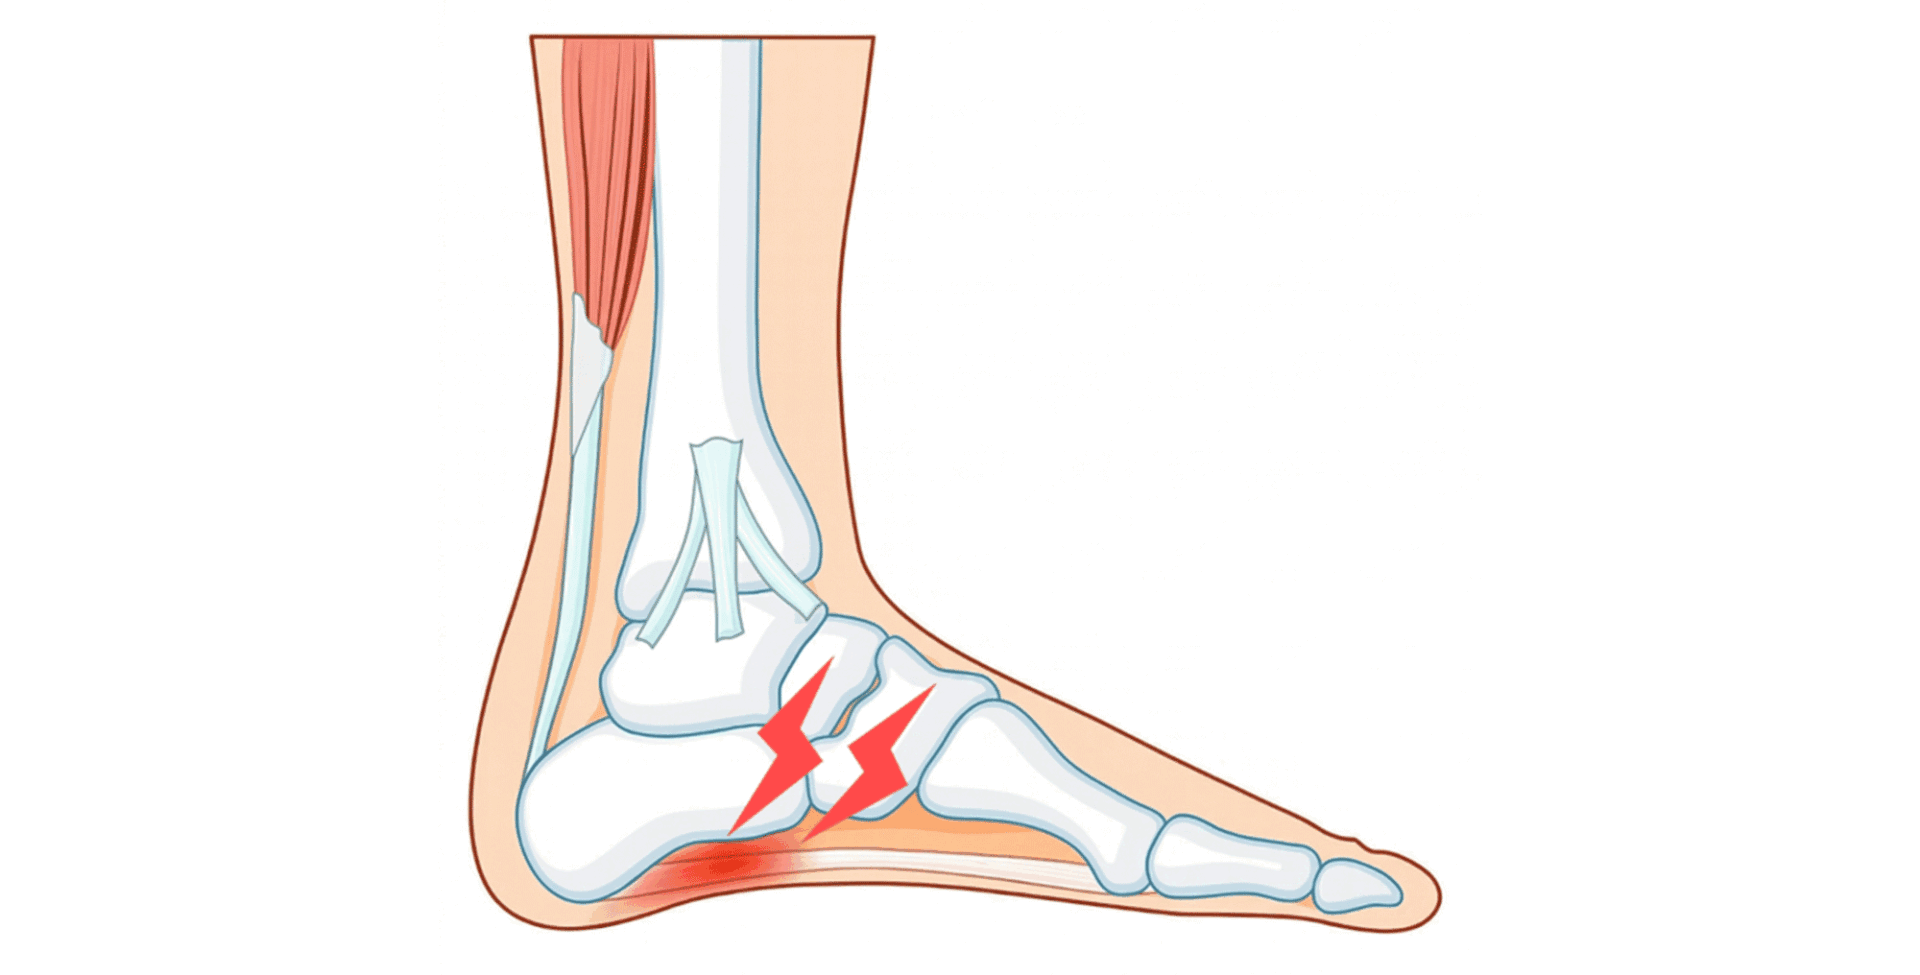

足底腱膜(足底筋膜)は、かかとの骨から足の指の付け根まで伸びる扇状の組織です。

歩くたびに体重を支え、足のアーチ構造を維持する重要な役割を担っています。

この組織の付着部に繰り返し負荷がかかることで微小断裂が蓄積し、変性が進んだ状態が足底腱膜症です。そのため病態の本質は炎症ではなく退行性変化(変性)です1)。